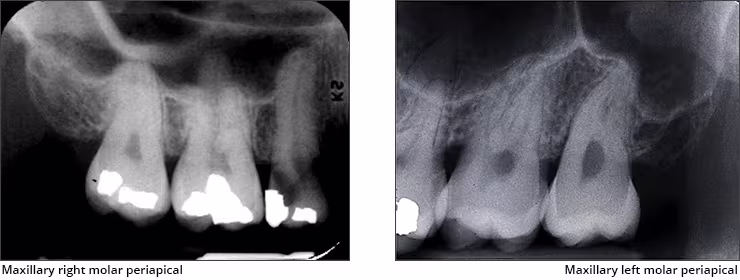

Maxillary sinus – The maxillary sinus is one of the paired paranasal sinuses. This prominent radiolucent air-filled cavity is located above the posterior teeth on the right and left sides of the maxilla. The sinus cavities are horizontally oblong bilateral structures with fine radiopaque borders. The maxillary sinus may contain septa which appear as radiopaque lines within the body of the sinus cavity. The size of the maxillary sinus can be quite variable and sometimes encroaches into the alveolar process, especially when posterior teeth are missing. Typically, the sinus appears uniform right to left. The maxillary sinus is sometimes referred to as the maxillary antrum and can be observed on both maxillary premolar and molar periapical images and partially on lateral-canine periapical images.

Zygomatic bone – The zygomatic bone or cheek bone attaches to the right and left sides of the posterior maxilla. The zygomatic bone, quadrangular in shape, broadens as it extends posteriorly. This bilateral radiopaque structure is also known as the malar bone. The zygomatic bone can be seen on maxillary premolar and molar periapical images.

Zygomatic process - The zygomatic process is the radiopaque U-shaped structure representing where the zygomatic bone attaches to the maxilla. The zygomatic process of the maxilla is the most anterior aspect of the zygomatic bone. The process is positioned toward the midline while the bone extends posteriorly away from the midline. This structure is sometimes referred to as the malar process and can be seen on maxillary premolar and molar periapical images.